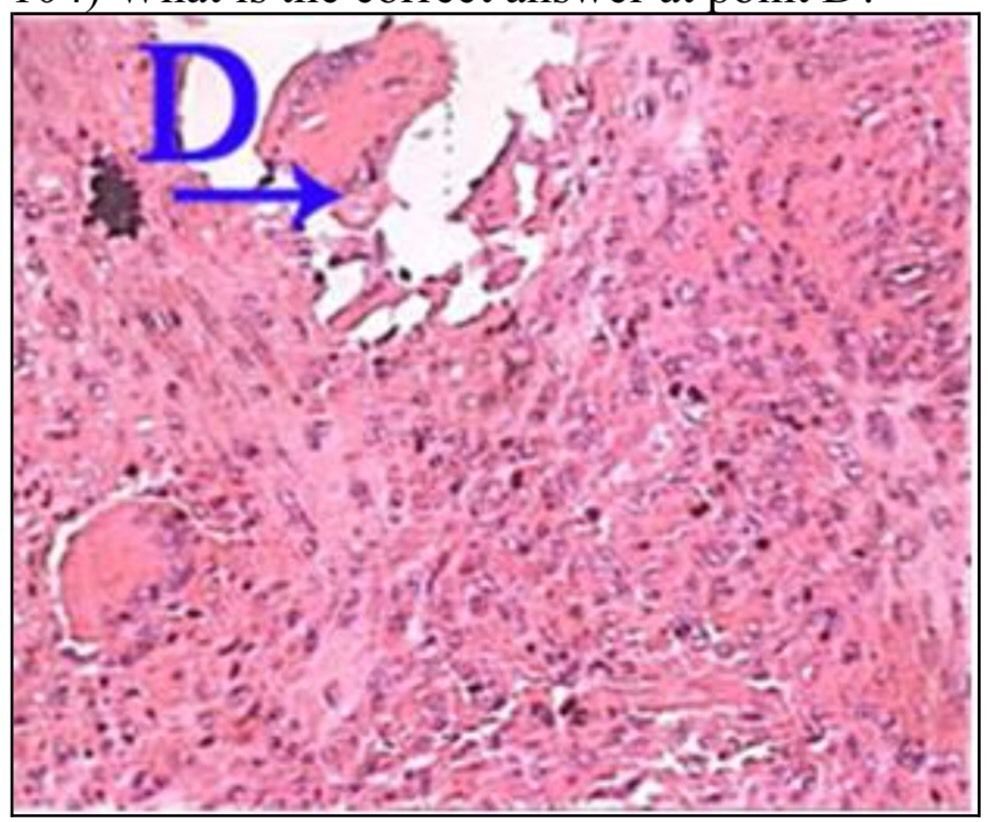

Question 4

Question

What is the correct answer at point D ?

Answer

• - épithélium exocervical normal

• - membrane basale

• - cellules anormales

• - épithélium dysplasique sévère

• - massifs carcinomateux